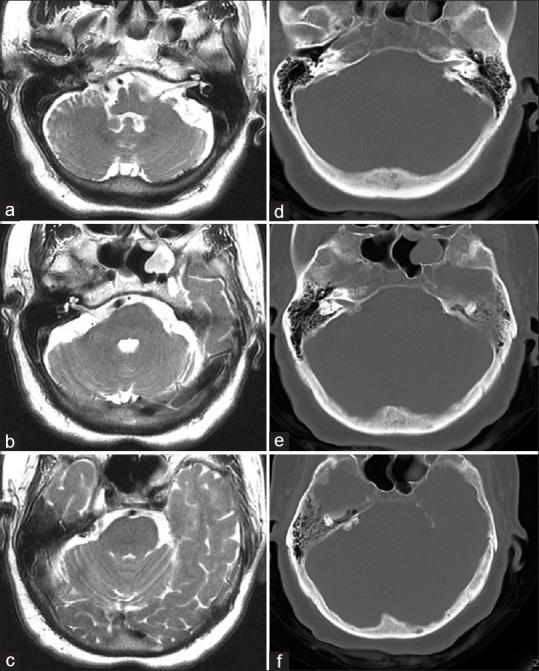

Osteomas and exostoses of cerebellopontine angle (CPA) are very rare, benign, and usually slow-growing lesions; few case reports have been published about these lesions in literature. The most common localizations of these temporal bone lesions are the mastoid cortex and the external acoustic canal. To our knowledge, only two cases of bilateral osteoma arising from both internal acoustic canals (IACs) have been reported. However, these tumors are usually asymptomatic and diagnose incidentally, and they can cause symptoms related to the 7 and 8 cranial nerve involvement. We report on a 75-year-old woman affected with bilateral osteoma of CPA and review the literature that 27 cases of IAC osteoma and exostoses have been reported.

桥小脑角(CPA)的骨瘤和外生骨疣非常罕见,为良性病变,通常生长缓慢;文献中关于这些病变的病例报告很少。这些颞骨病变最常见的部位是乳突皮质和外耳道。据我们所知,仅有两例双侧内耳道(IAC)骨瘤的报道。然而,这些肿瘤通常无症状,多为偶然诊断,也可引起与第Ⅶ和Ⅷ颅神经受累相关的症状。我们报告了一例75岁患有双侧CPA骨瘤的女性病例,并回顾了文献,其中已报道27例IAC骨瘤和外生骨疣病例。